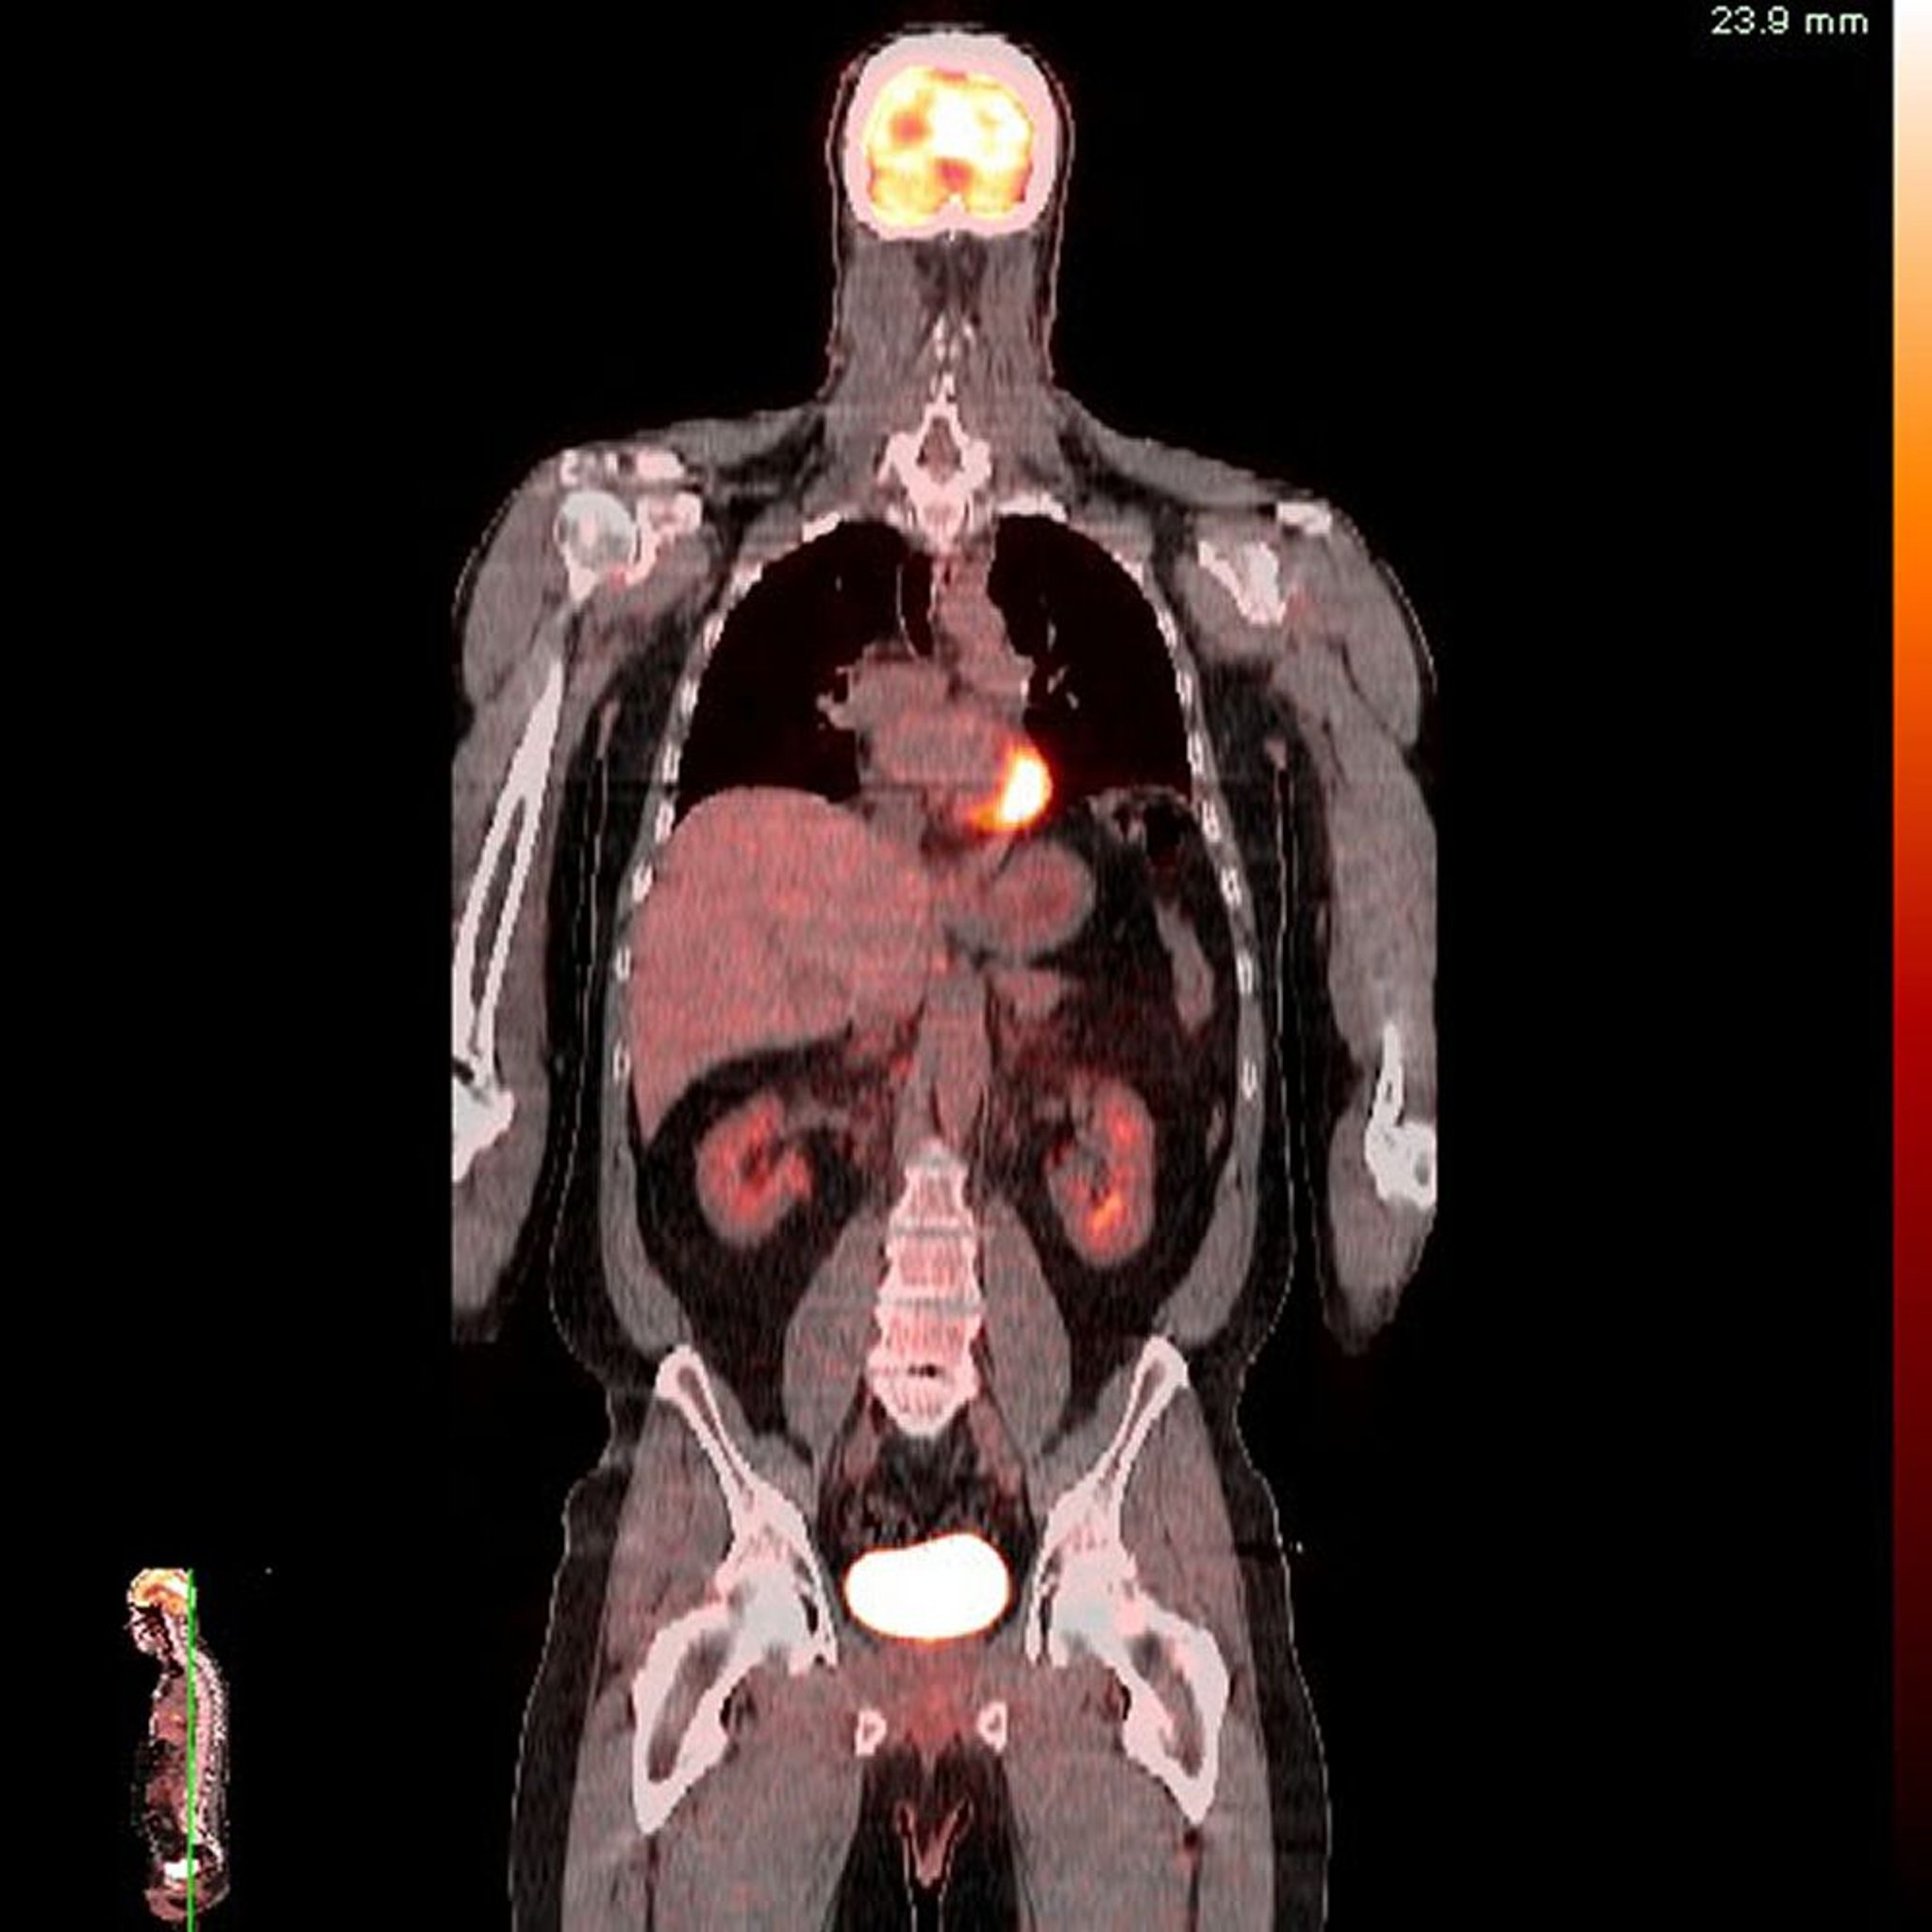

Позитронно-эмиссионная томография-компьютерная томография (ПЭТ-КТ)